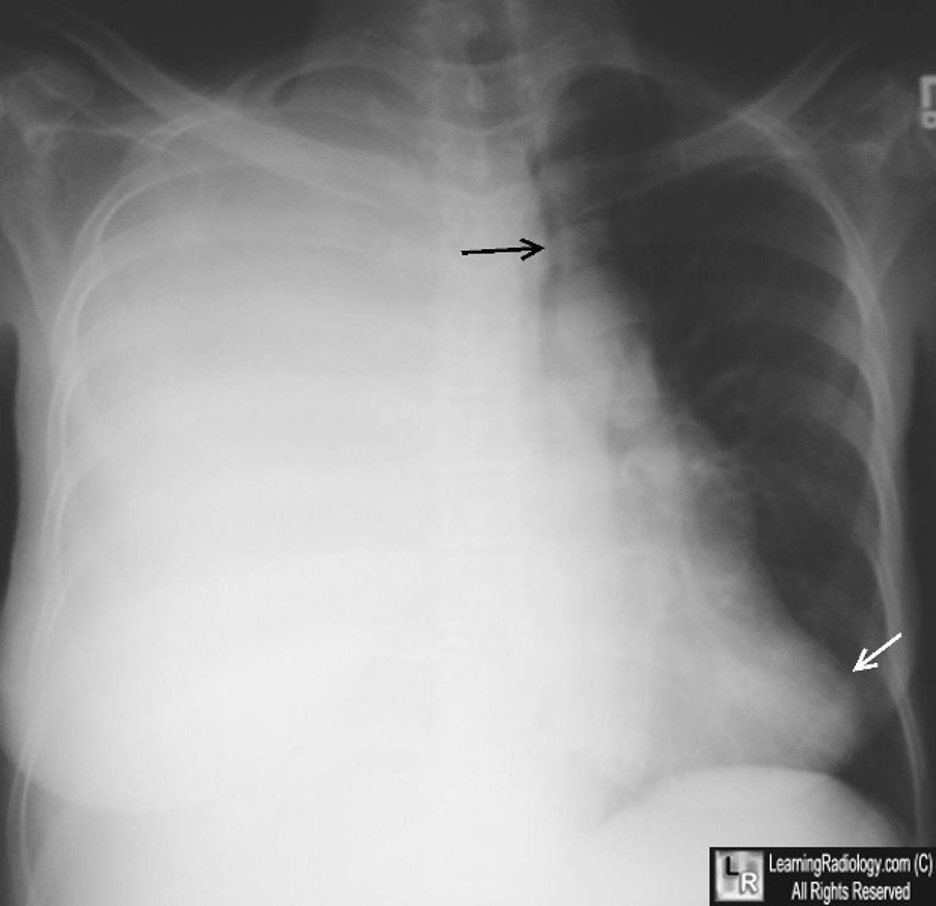

9/ One of the  https://abs.twimg.com/emoji/v2/... draggable="false" alt="🔑" title="Schlüssel" aria-label="Emoji: Schlüssel"> features of lung entrapment is an improvement in dyspnea following a thoracentesis. However, the lung does not fully expand radiographically following the procedure. CT imaging may show a visceral pleura that appears thickened, nodular, or hyperechoic.

https://abs.twimg.com/emoji/v2/... draggable="false" alt="🔑" title="Schlüssel" aria-label="Emoji: Schlüssel"> features of lung entrapment is an improvement in dyspnea following a thoracentesis. However, the lung does not fully expand radiographically following the procedure. CT imaging may show a visceral pleura that appears thickened, nodular, or hyperechoic.

10/ With large pleural effusions, you typically get a contralateral shift of the mediastinum. However, with lung entrapment you will typically see the mediastinum shift ipsilaterally of the effusion or no shift at all. @CritCareMed @PulmCrit @MedEdPGH @gradydoctor